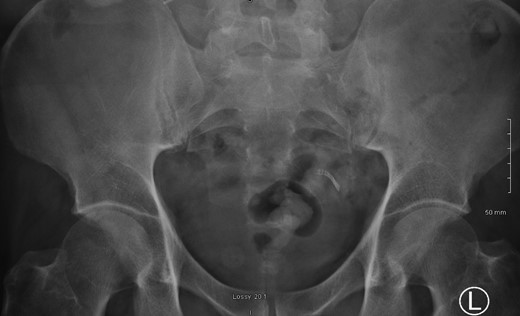

A 52-year male was referred to the surgical team for a 1-day history of left iliac fossa pain accompanied by nausea and the inability to open his bowels for 48 hours. The pain was 9/10 in severity, sharp, persistent and with a gradual worsening onset. The patient was previously diagnosed with extensive diverticular disease and admitted 2 months prior with acute sigmoid diverticulitis. 18 months earlier he underwent an emergent laparoscopy for an unclear pelvic inflammatory mass on CT, that suggested either severe sigmoid diverticulitis or appendicitis. He also had multiple polyps throughout the colon, that were endoscopically removed. The patients past medical history was significant for a non-flow limiting coronary artery disease, arterial hypertension and an allergy to penicillin and tetracycline. Temperature on admission was 38.7 C, blood pressure of 149/109 mm/Hg, pulse of 109 bpm and a respiratory rate of 20/min with O2-saturations of 96% on room air. The abdomen was soft with tenderness and guarding over the left iliac fossa. Bowel sounds were present. Investigations showed a white cell count of 17.6 tsd/ul and a CRP of 64 mg/l. No pneumoperitoneum was detected on an erect chest x-ray. Treatment with ciprofloxacin and metronidazole was started and the patient kept nil per mouth. CT imaging showed extensive sigmoid diverticular disease with marked pericolonic fat stranding and free gas tracking into the mesenteric fat. Gentamycin was added and within 3 days the patient’s clinical symptoms improved. He was apyrexic and the white cell count dropped to 10.9 tsd/ul. A repeat CT scan showed a stable appearing localized perforation with reduced free gas and no signs of collection. However, of note was a small curvilinear metallic foreign body within the lumen of the sigmoid colon of uncertain etiology (Fig. 1). On questioning, the patient recalled a mechanical fall with a head contusion 9 days prior to admission during which he lost his partial denture. The patient was commenced on laxatives and despite bowel movement on the following day, the foreign body did not pass. A PFA showed the persistent presence of the metallic foreign body over the sigmoid colon, which raised the suspicion of impaction (Fig. 2). The patient was prepared for colonoscopy and the foreign body was identified impacting the lumen of the sigmoid colon (Fig. 3). However, endoscopic retrieval failed and the decision was made to proceed with laparoscopic anterior resection. Intraoperative findings showed a rigid and thickened sigmoid colon with adhesions and a diverticular abscess. About 22 cm of sigmoid colon was resected and the procedure was completed with a primary colo-rectal end to end anastomosis, using a 31 mm CEEA-Stapler. The resected sigmoid colon contained the lost partial denture, which showed impaction and perforation into the sigmoid mesocolon (Fig. 4). Following surgery, the patient was transferred to the surgical ICU for 24 h observation and discharged home after one week.

22 cm of resected sigmoid colon contained the lost partial denture showing impaction and perforation into the sigmoid mesocolon.